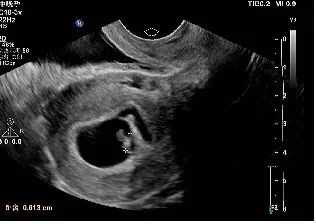

【一超二超照片】

一超

2019年10月18日一超:宫腔内见胚囊,大小17*21*22mm,胚芽长6mm,胎心136次/分。血β-、孕酮27.35、雌二醇373.12。